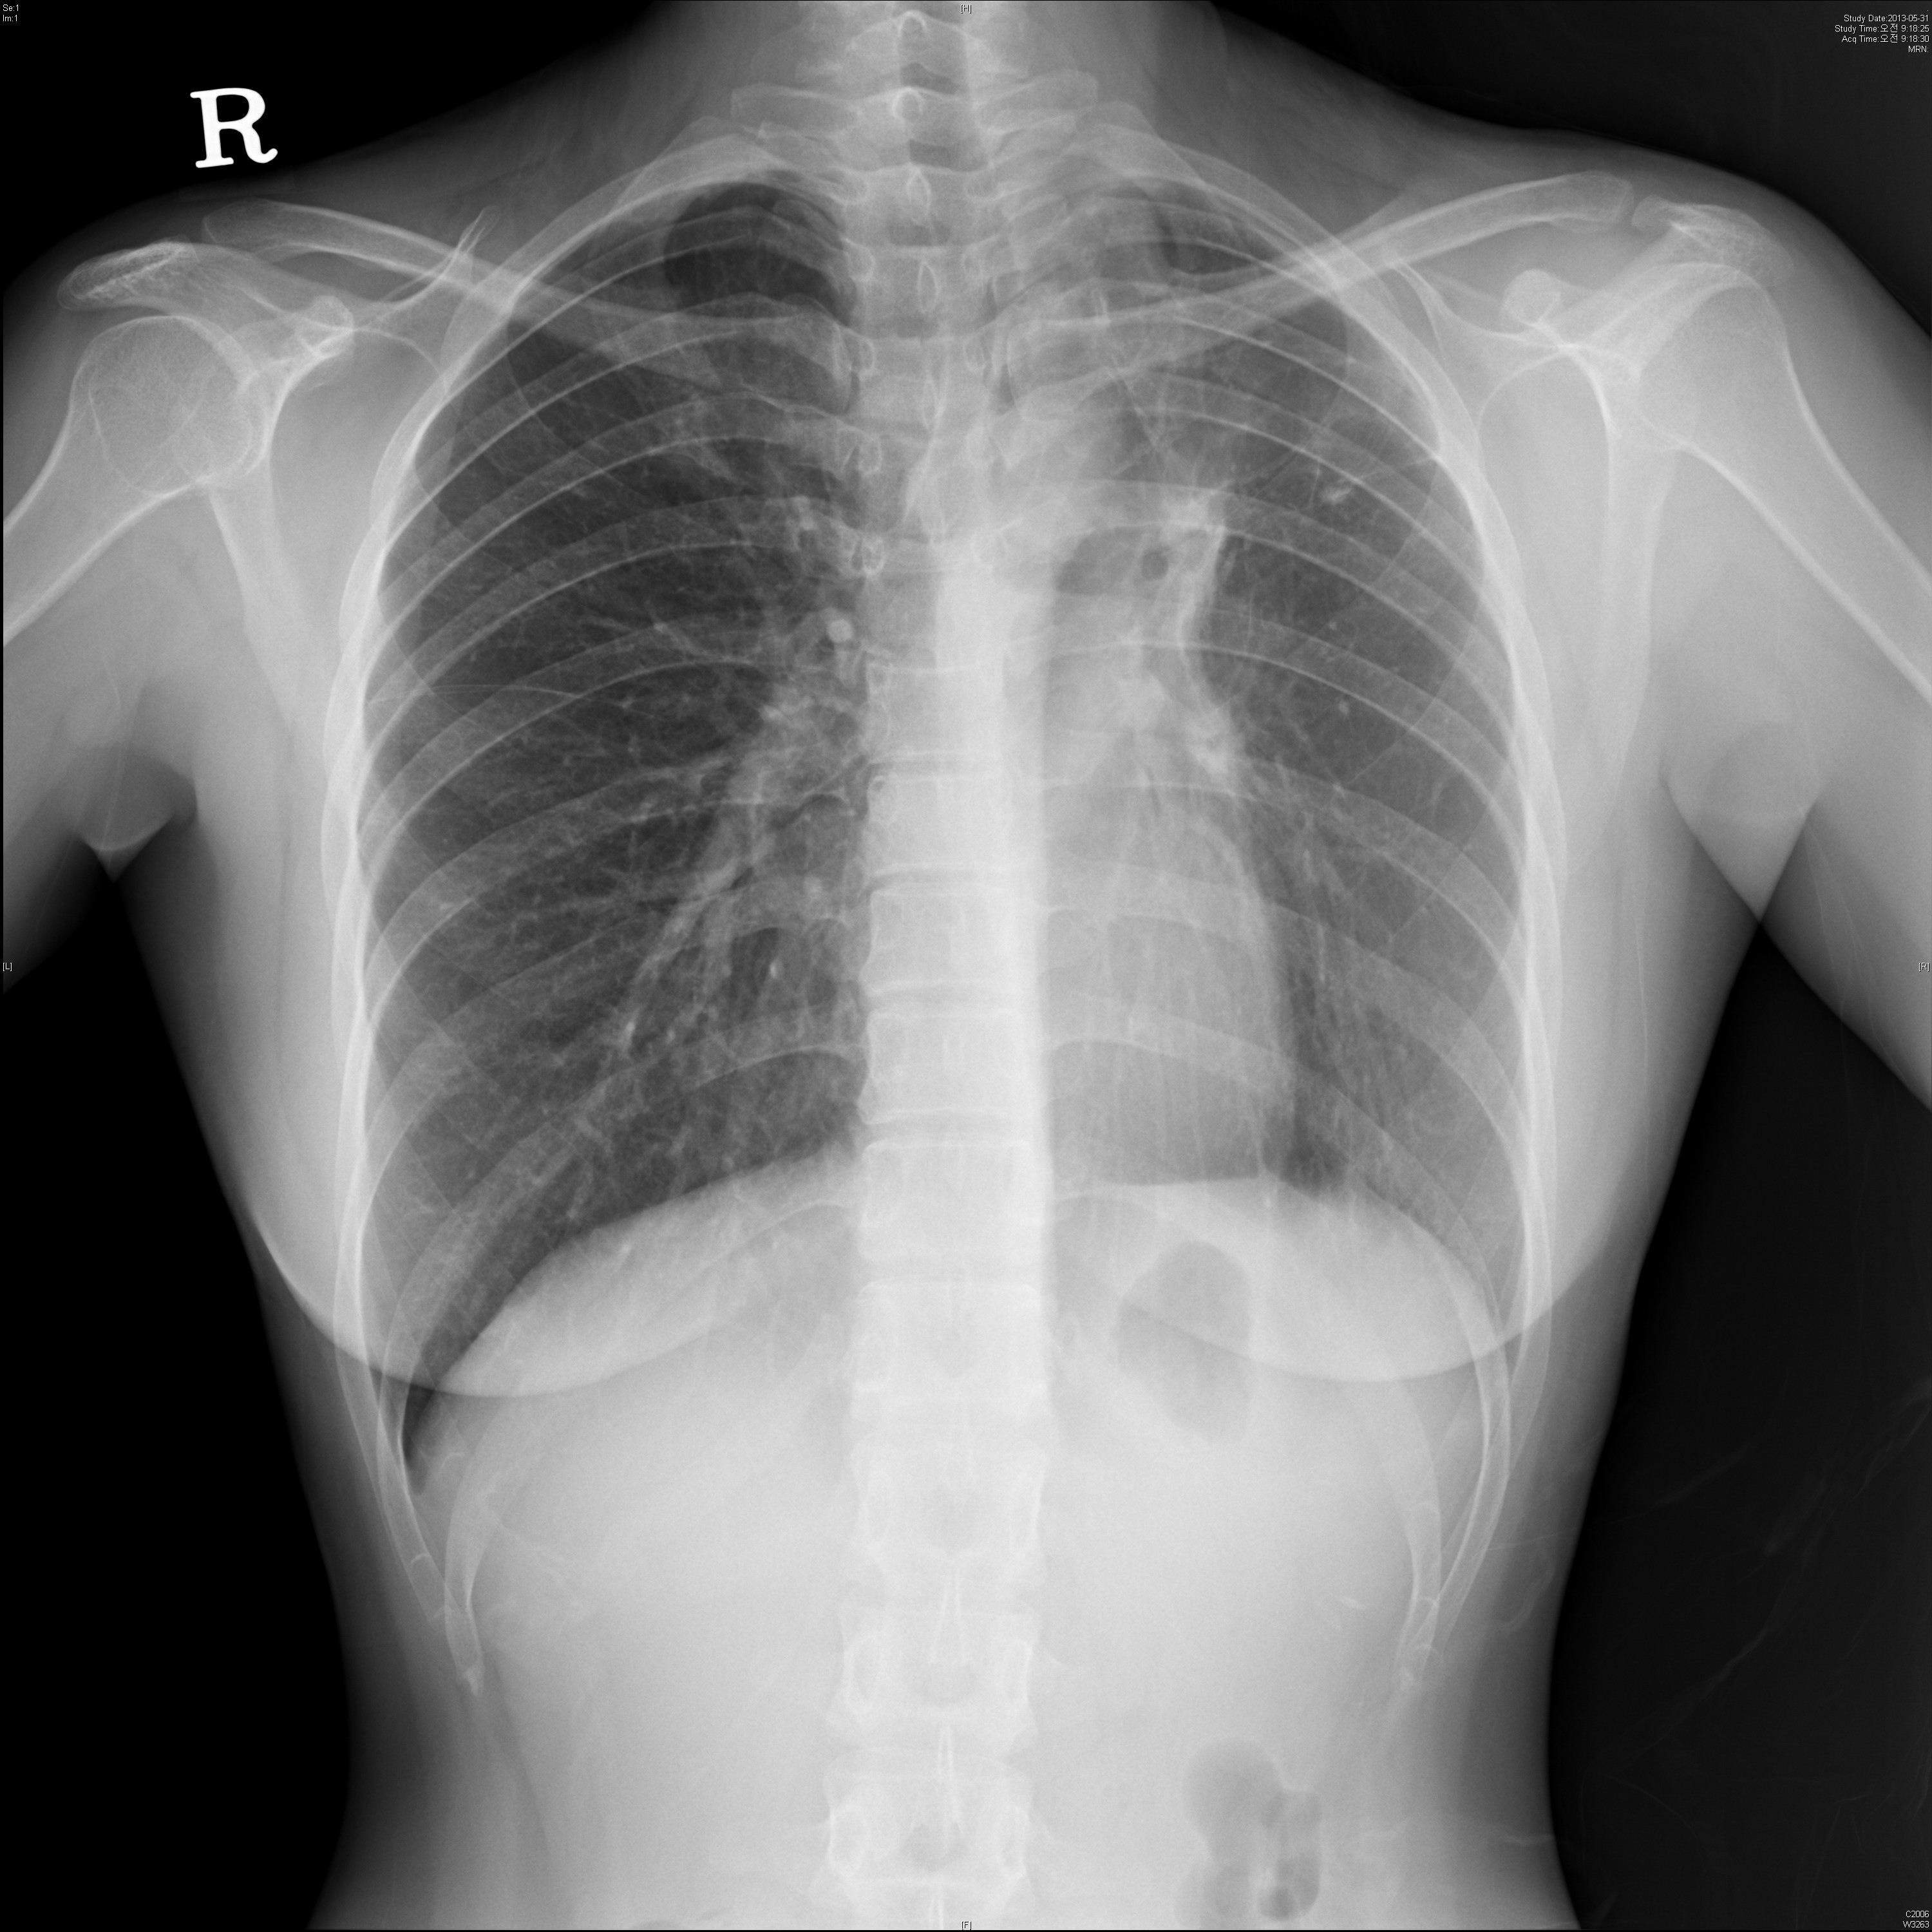

34¼¼ ¿©ÀÚÀÔ´Ï´Ù. TBÀÇ º´·ÂÀÌ ÀÖ½À´Ï´Ù.

´ÙÀ½ chest PA ¹× Lat(Lt)¿¡¼­ ¾Ë ¼ö ÀÖ´Â ÀÌ»óÀº ¹«¾ùÀϱî¿ä?